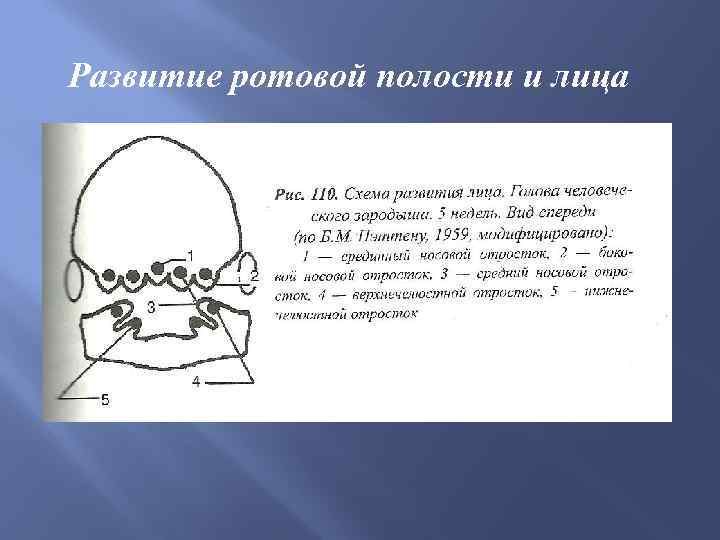

Развитие ротовой полости и лица

Развитие ротовой полости и лица